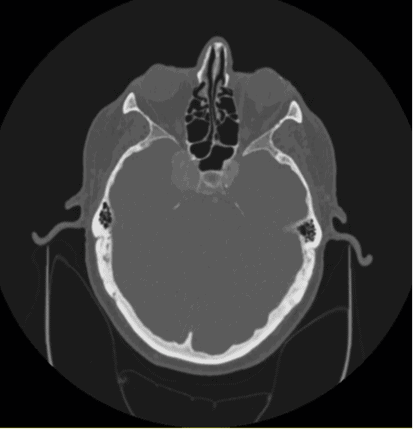

An 84-year-old Caucasian man with a history of hypertension and chronic obstructive pulmonary disease presented to the eye clinic with complaints of diplopia. A month prior to this visit, he was diagnosed with restrictive strabismus in supraduction of the right eye following entropion and ptosis repair of the right eye. However, at this following visit, the right eye also had restrictions of adduction, supraduction, and infraduction. Additionally, he presented with moderate neurogenic ptosis of the right upper eyelid, and his right pupil was large and non-reactive and there was no APD by reverse testing. Visual acuities were 20/20 right and left eye. He was diagnosed with a right cranial nerve three palsy and sent to the emergency room for an urgent evaluation. The potential differentials of a cranial nerve three palsy were explored, including giant cell arteritis, vascular etiologies, trauma, intracranial neoplasm, intracranial hemorrhage, and cerebral aneurysm. Trauma was not supported by patient history and ESR, CRP, and CBC were normal. CT and CTA scan revealed a giant intracranial cavernous aneurysm of the right internal carotid artery (Figure 1).

Figure 1. CT (inferior coronal view) without contrast showing complex giant intracranial cavernous aneurysm of the right internal carotid artery, measuring 25 mm anteroposterior x 16 mm transverse x 18 mm caudocranial. MRI and MRA of original aneurysm were unavailable for this case report.